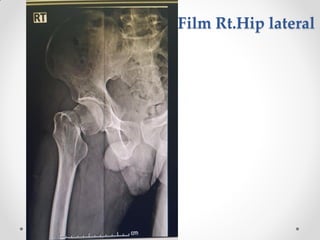

Film Rt.Hip lateral

Film Rt.knee AP-lateral